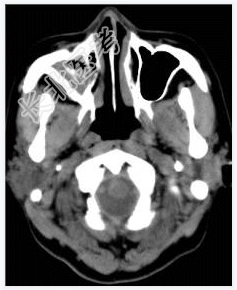

- [材料题] 女性,50岁。鼻塞2年余,有异物感,有血性分泌物,伴面颊疼痛。行CT检查。

- 简答题1、患者的诊断及依据是什么?

- 简答题2、需要与哪些疾病鉴别?